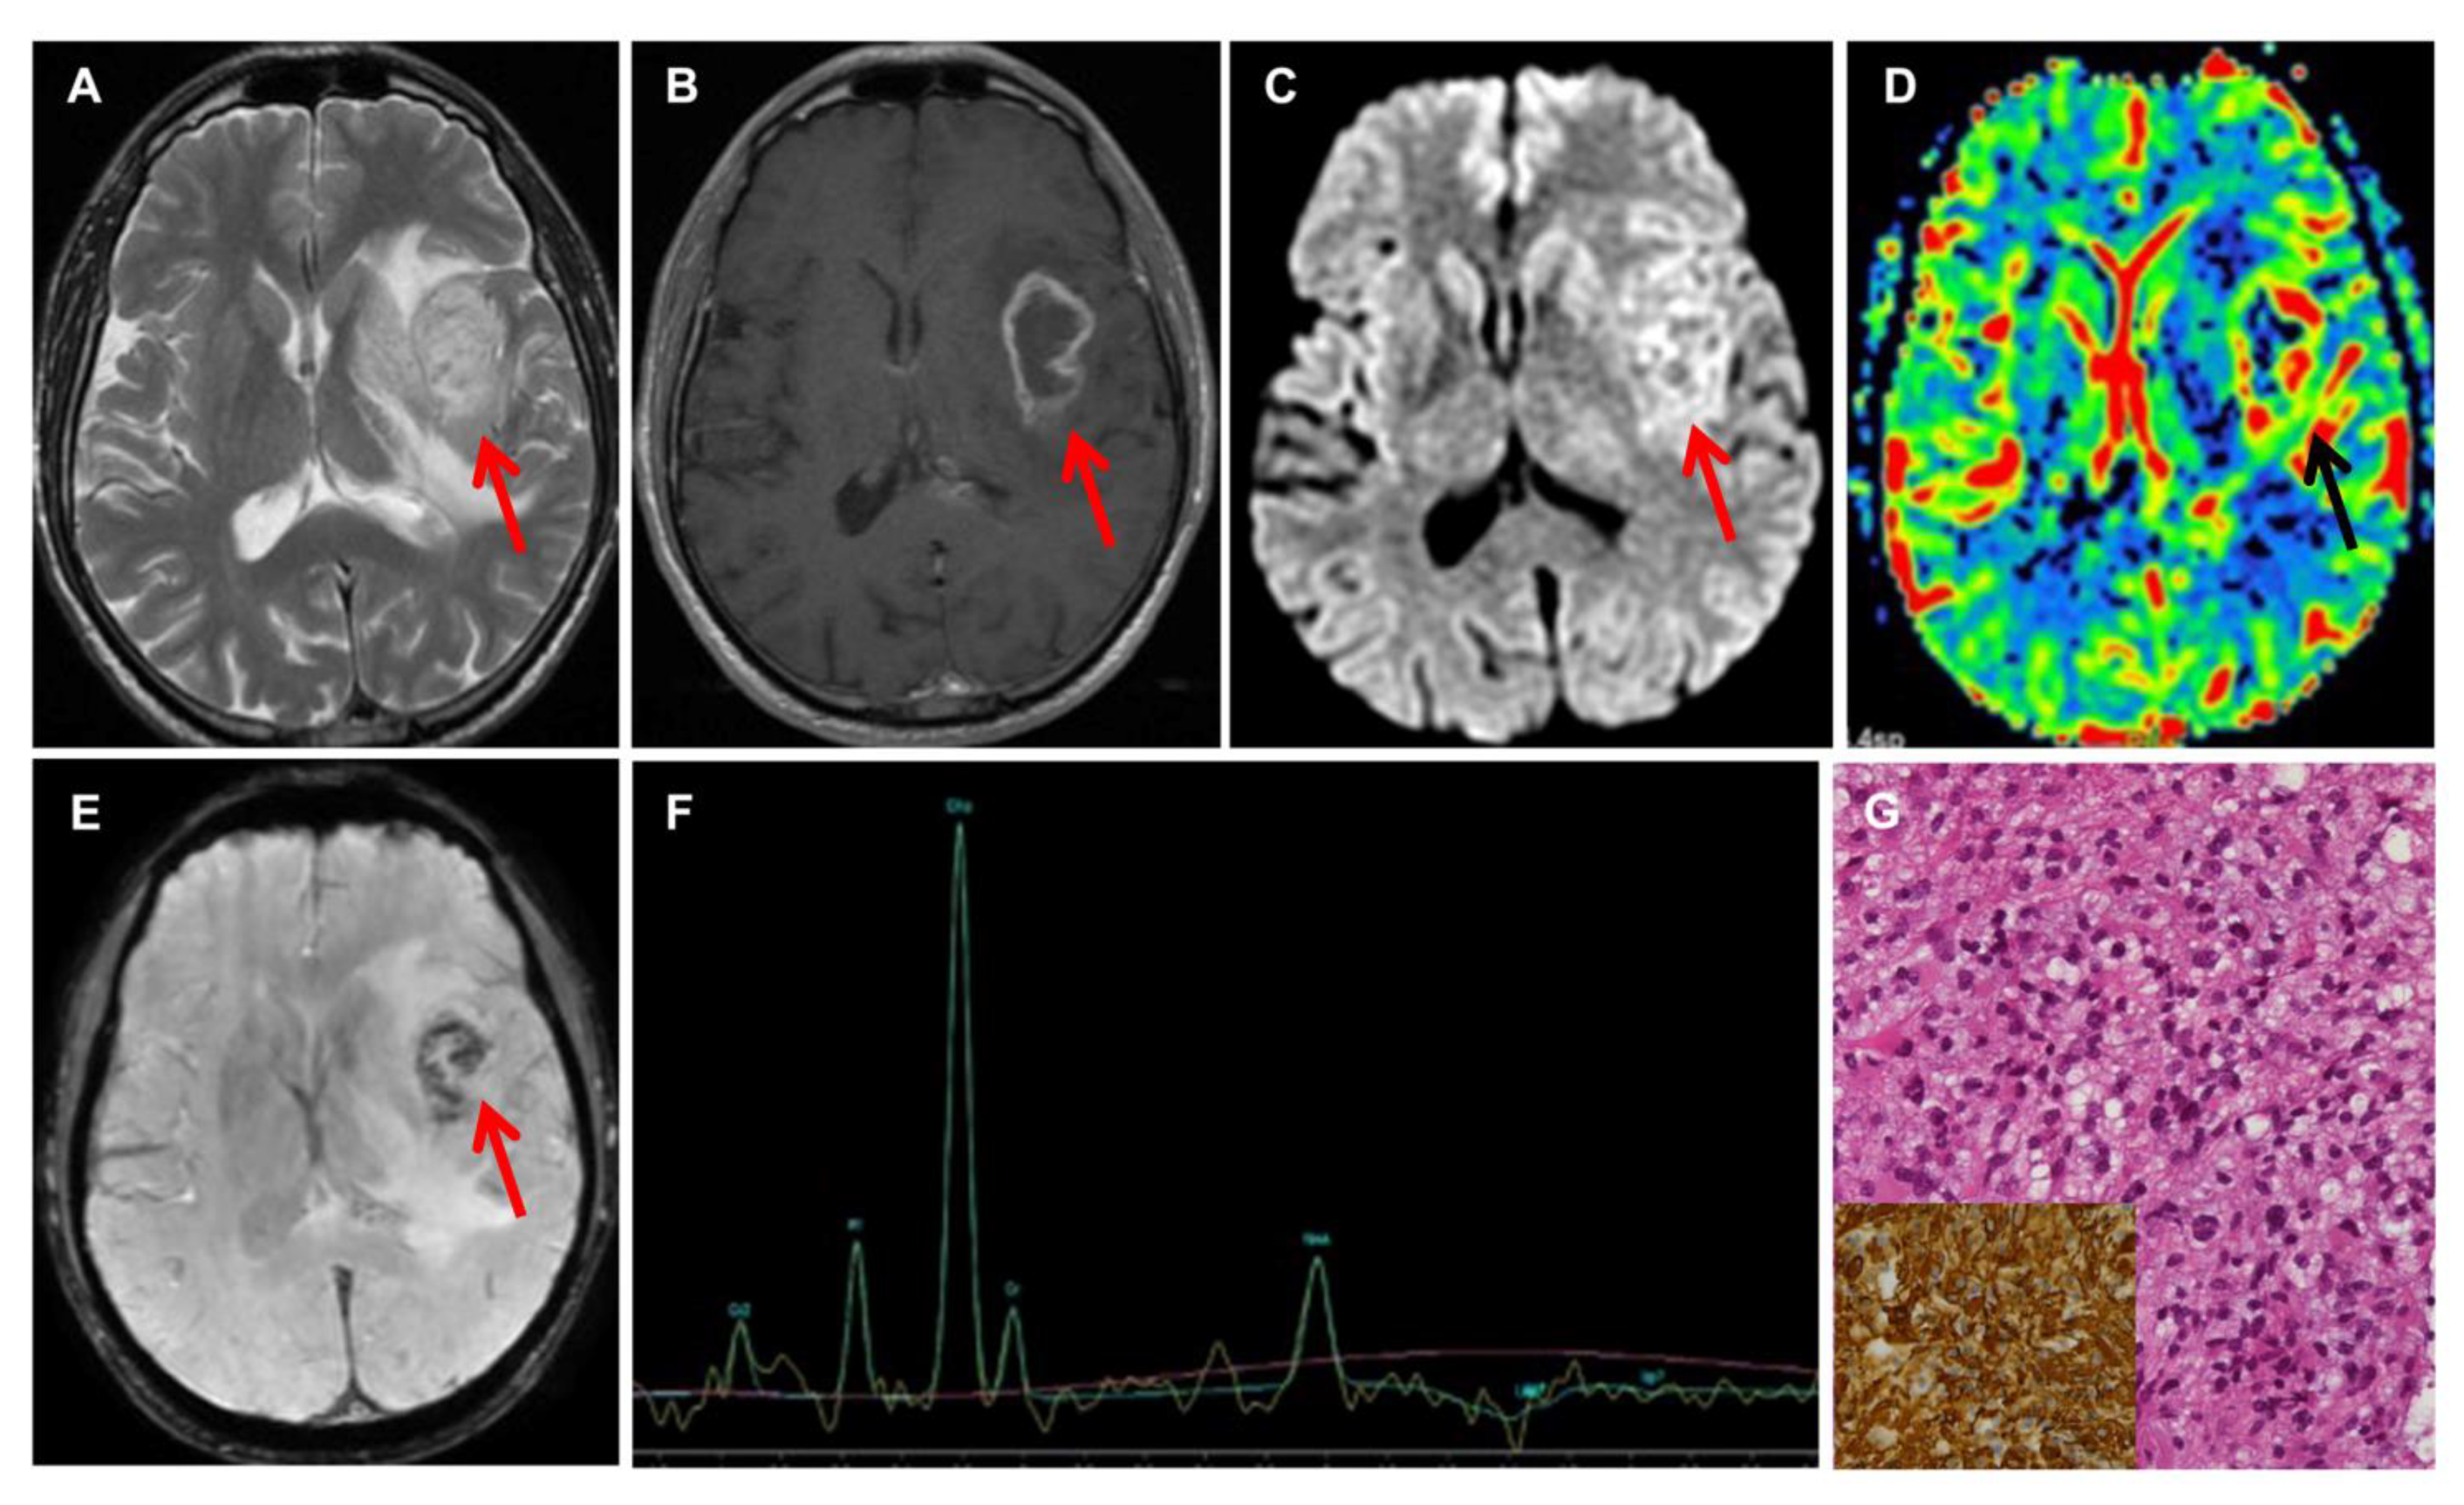

2.2. Radiological Evaluation

3.4. Follow-Up of Biopsy Patients